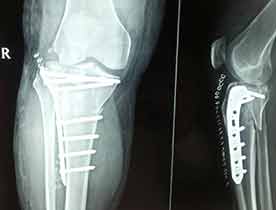

Case:5 Intra-Articular Upper End Tibia

Patient, aged 40 years male following vehicular accident sustained depressed fracture Intra-Articular upper end of right Tibia. Aspiration of right knee done and above knee slab was given for stabilisation. Operated next day with open reduction + elevation of depressed fragment with Edelend’s Technique & fixation with lateral locking plate fixation.

Pre-Op

Post-Op